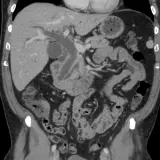

Over 2,100 interactive radiology cases, curated by radiologists for your level of training. Scroll, window, and view cases full screen — just like on PACS. Click linked findings in each writeup to jump straight to them on the image. Cases include sample reports, a focused discussion section, original illustrations, and videos.

Our site includes 3 main courses: Call Preparation, Introduction to Radiology, and Neuro Fellowship.

Call Preparation — our comprehensive curriculum for junior residents preparing for call covering both classic and atypical presentations. Use the call simulator to practice a real call shift — shuffle cases, enter your own preliminary report, and receive constructive AI feedback.